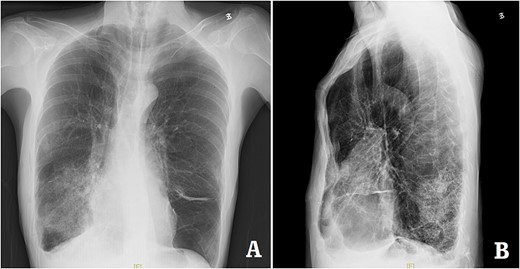

The patient was a 29-year-old male. He was found to have protrusive deformity on the anterior chest wall since childhood. The deformity was not serious in early years, but worsened after adolescence, with the lower part of the sternum protruding at an acute angle. At the age of 25, he developed right spontaneous pneumothorax and received surgical treatment at local hospital, but his thoracic deformity was not treated. As the deformity continued to worsen, which seriously affected the appearance of the chest wall, the patient was admitted to our hospital for surgery. Preoperative physical examination showed that the anterior chest wall was protrusive seriously, with a sharp tip protruding forward. The rib arches on both sides were slightly depressed (Fig. 1). Imaging examination showed that the anterior chest wall was protrusive, and the lower end of the sternum was at the forefront of the protrusion. His heart moved to the right, and the rib arches were slightly depressed (Figs 2–4). The operation was performed under general anesthesia. Two longitudinal incisions were made on both sides of the chest wall respectively. The incisions were located between the front axillary line and the median axillary line, with the length of ~5 cm. The chest wall muscles were dissected to expose the ribs in the incisions. Two tunnels were made on the highest plane of the protrusion, with interval of 3 cm. The tunnels were located in the deep layer of the chest wall muscles and bone structures. Two steel bars were inserted into the tunnels to flatten the front protrusion with their median parts, and then, both ends of the steel bars were fixed on the ribs at the lateral chest wall. The above operation was the main content of Wenlin procedure [1, 2, 5]. After this procedure was completed, the lower part of the chest wall showed obvious depression, especially in the middle of the rib arches. Then, Wung procedure was performed [6]. A third tunnel was made at the plane passing the midpoint of the rib arch, which passes through the bilateral thoracic cavity. The third steel bar was inserted into the tunnel. After the steel bar was rotated and fixed to the ribs, the depression was supported totally. The incisions were closed, and the operation was completed. The deformity of anterior chest wall disappeared completely after the operation (Fig. 5). The operation time was 75 min. The intraoperative bleeding volume was 40 ml. Postoperative X-ray examination showed that the bars position was normal (Fig. 6). He was discharged 7 days after operation. Follow up for 1 year showed satisfactory recovery. The steel bars were taken out 1 year after the operation, and the appearance of the thorax was normal and there was no recurrence (Fig. 7).

X-ray examination after operation. (A) Posteroanterior radiograph; and (B) lateral radiograph.